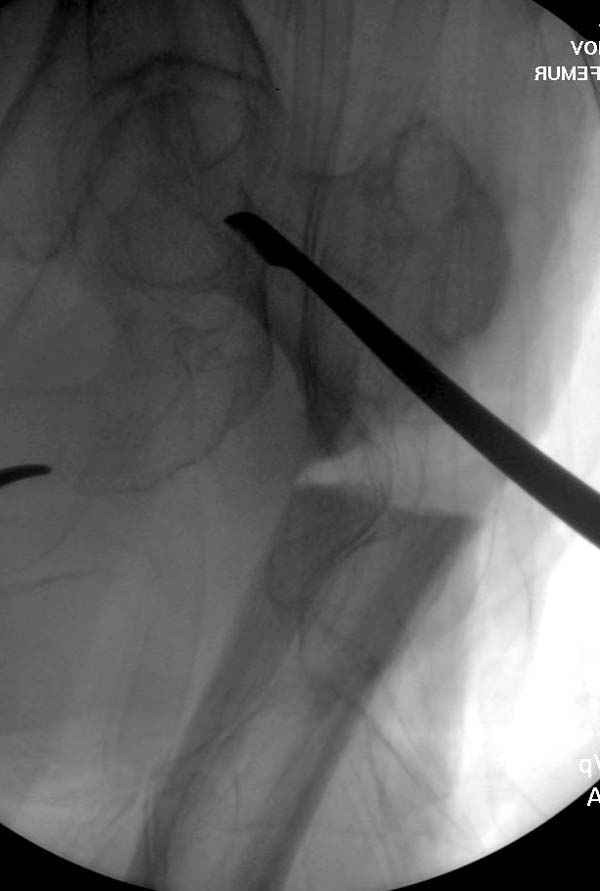

Не стали усложнять интрамедуллярным вариантом коррекции, легче контролировать коррекцию пластиной, поэтому сделали операцию 95 градусной Blade Plate, разогнув до 110 градусов.

Надеемся на успех, потому что до введения пластины дефект от импланта забили костной стружкой и удалось создать компрессию между отломками, максимальную для импланта (150 кило/паунд). Сделана дополнительная костная пластика и за счет измененного угла пластины устранено укорочение конечности.

Страйкер предоставил отличный инструмент - крючок для удаления длинного гвоздя. Считаем, что врачебная ошибка по установке привела к несостоятельности импланта и к ятрогенному осложнению.